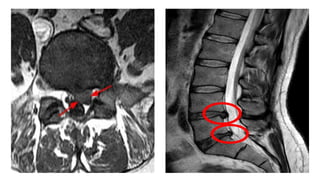

Clinical Relevance: Intervertebral Disc Herniation

• The intervertebral disc is a fibro-cartilaginous cylinder that lies between

the vertebrae, joining them together. They permit the flexibility of the

spine, and act as shock absorbers. In the lumbar and thoracic regions,

they are wedge–shaped – supporting the curvature of the spine.

• Each vertebral disc has two parts: the nucleus pulposus and annulus

fibrosus. The annulus fibrosus is tough and collagenous, and it surrounds

the jelly-like nucleus pulposus.

• Herniation of an intervertebral disc occurs when the nucleus

pulposus ruptures, breaking through the annulus fibrosus. The rupture

usually occurs in a posterior-lateral direction, after which the nucleus

pulposis can irritate nearby spinal nerves – resulting in a variety of

neurological and muscular symptoms.